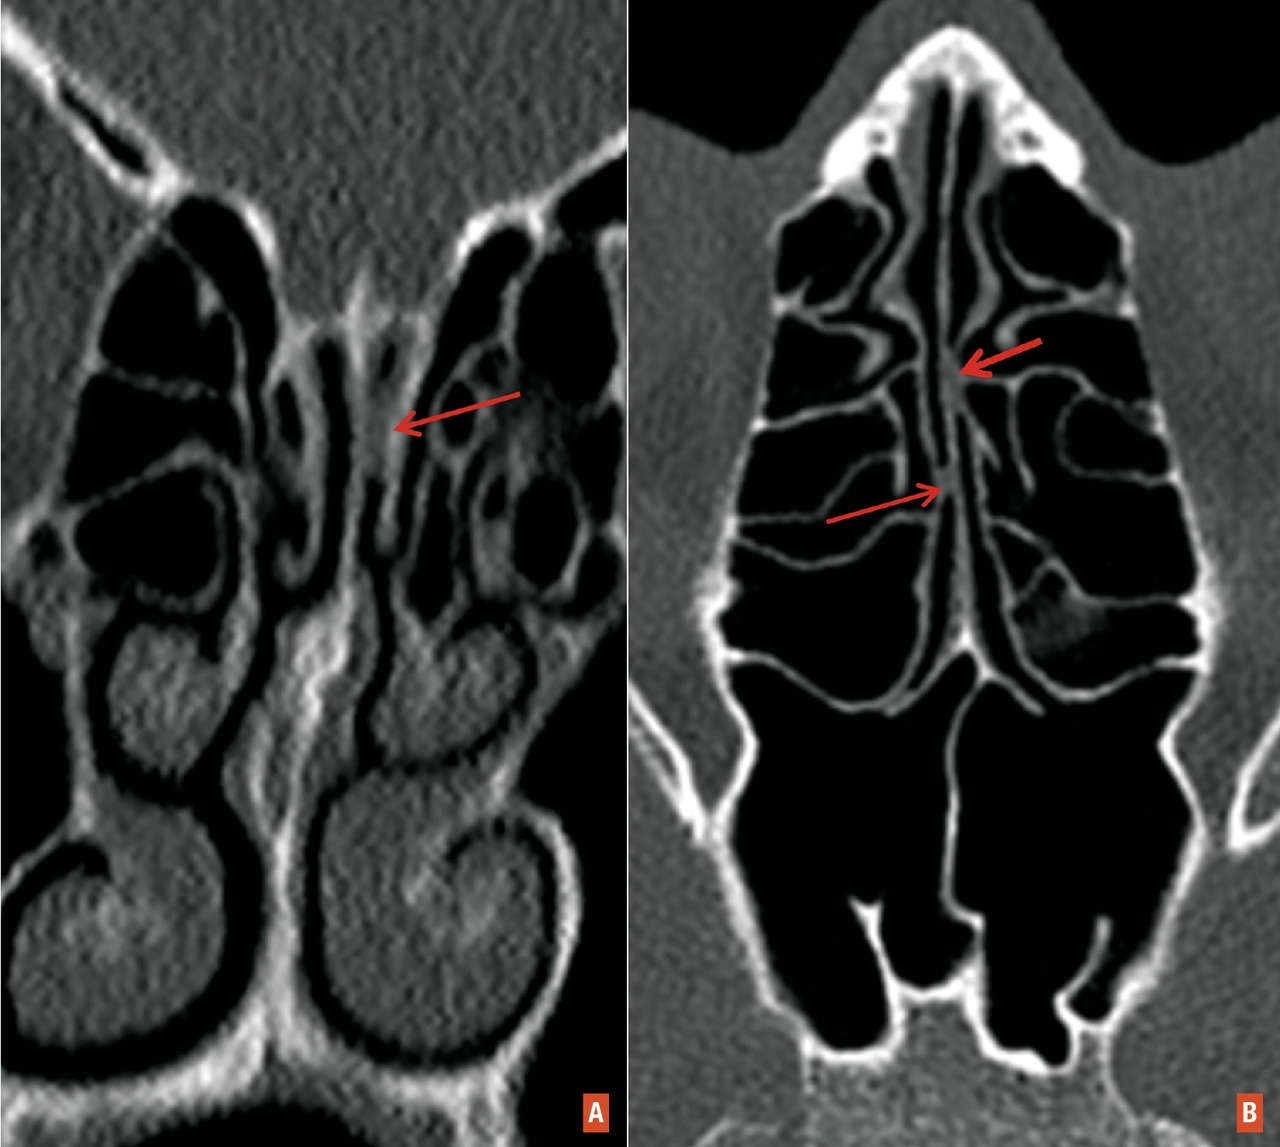

L’inflammation/destruction de la muqueuse olfactive est objectivée sur la tomodensitométrie et l’imagerie par résonance magnétique (IRM) nasosinusiennes. On observe, pendant la phase aiguë, des opacités complètes ou quasiment complètes des récessus olfactifs chez les patients Covid-19 ayant une perte brutale de l’odorat (fig. 2 ). Ces anomalies sont souvent isolées, sans atteinte des sinus paranasaux ni des cavités nasales. Ces opacités diminuent ou disparaissent au fil du temps lorsque les patients ont récupéré totalement leur odorat.

Nous supposons que ce traitement permet de réduire l’inflammation de la muqueuse olfactive pour limiter la destruction des neurones sensoriels olfactifs et réduire le phénomène de sclérose de la muqueuse olfactive pendant la procédure de cicatrisation, limitant ainsi la sténose des fentes olfactives séquellaires. À partir de nos expériences, un traitement par corticoïdes à distance (au-delà de 6 semaines) chez les patients ayant eu une Covid-19 n’améliore pas leurs troubles de l’odorat malgré la présence d’opacités au niveau de la muqueuse olfactive sur le scanner nez-sinus. À ce niveau, ces opacités sont probablement dues à la sclérose. Le traitement par corticoïdes intranasaux est peu convaincant, car les molécules médicamenteuses n’atteignent que difficilement la muqueuse olfactive située dans une région très haute et étroite des cavités nasales. D’autre part, les lavages de nez à la seringue au sérum physiologique sont aussi à envisager, comme les soins des autres plaies cutanées ou de la muqueuse. Ces lavages permettent probablement de nettoyer les débris muqueux au niveau des fentes olfactives (dont la localisation est haute, nécessitant l’utilisation des seringues de 10 ou 20 mL), favorisant la cicatrisation et réduisant les synéchies à cet endroit. L’irrigation intranasale précoce par sérum physiologique versus celle à partir du 7e jour après la perte de l’odorat reste encore une question à résoudre. Théoriquement, plus les soins locaux sont faits tôt, mieux les plaies cicatrisent, avec une fibrose cicatricielle réduite. Des lavages précoces permettent-ils une accélération de la clairance virale locale ou au contraire facilitent-ils une dispersion du virus ? Ce sont des hypothèses à clarifier. Au-delà d’une semaine, le risque de disperser le virus est très faible, mais la cicatrisation de la muqueuse olfactive a déjà commencé.

Pour les patients qui ont une perte de l’odorat persistante au-delà de 8 semaines, un bilan ORL complet associant endoscopie nasale, test de l’odorat, questionnaire évaluant l’impact des troubles de l’odorat dans la vie personnelle et professionnelle est nécessaire. Il s’agit aussi de chercher d’autres pathologies associées (rhinite allergique, polypose nasale…) qui sont également des causes de troubles de l’odorat. Un examen tomodensitométrique nez-sinus est également recommandé, à la recherche d’anomalies au niveau des récessus olfactifs, telles qu’une sténose, des opacités, des synéchies de la muqueuse… Une rééducation olfactive sur une longue durée (au minimum 16 semaines) est fortement conseillée, car cette méthode a prouvé son efficacité dans la perte de l’odorat post-infectieuse.39